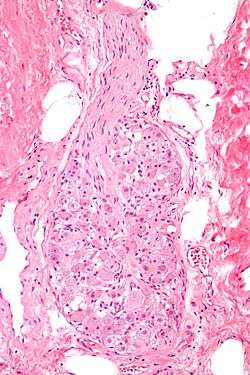

![]() Micrograph of a ganglion. H&E stain. | |